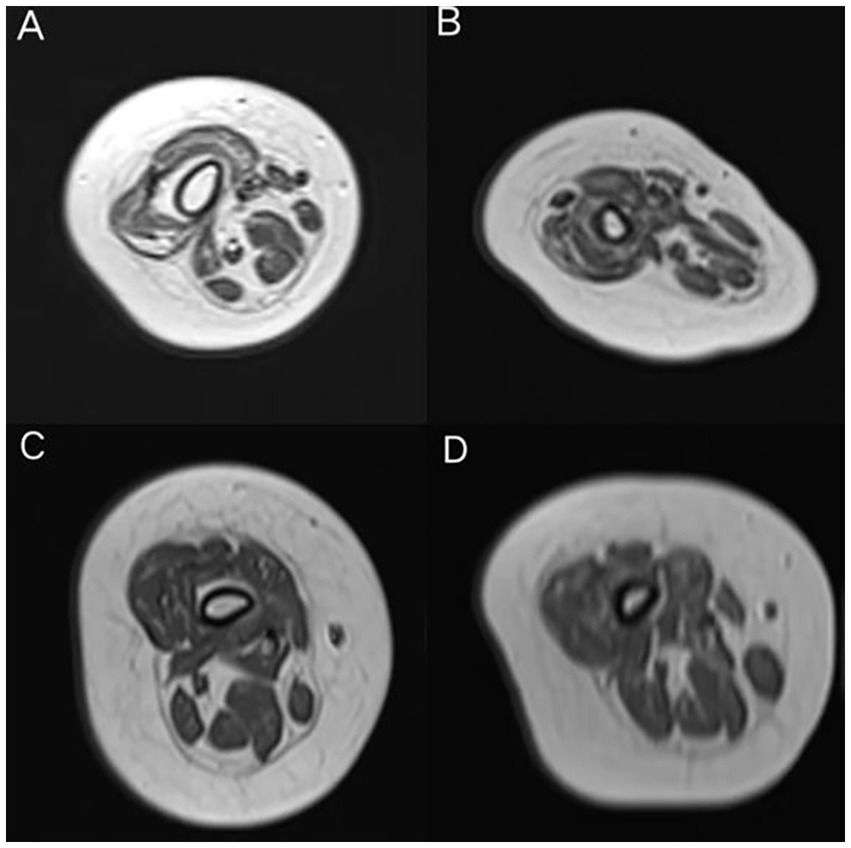

The grade of the two groups of patients were compared, and the results are shown in Table 4. There were no significant differences in the modified Mercuri scores between the two groups at baseline and at 14 months of treatment (p = 0.159 and p = 0.405, respectively). However, within the rehabilitation group, one patient showed mild alleviation in the degree of fatty infiltration in the quadriceps muscles at 14 months of treatment (from grade 4 to grade 3), while no such improvement was observed in the patients of the non-rehabilitation group (Figure 5).

Figure 5

MRI images of the thigh muscles of a patient from the rehabilitation group at baseline (A) and at 14 months of nusinersen treatment (B). At 14 months, there was a slight alleviation in the degree of fat infiltration in the quadriceps femoris (from grade 4 to grade 3). MRI images of the thigh muscles of a patient from the non-rehabilitation group at baseline (C) and at 14 months of nusinersen treatment (D). There was no significant change in the degree of muscle fat infiltration between baseline and 14 months.

Douglas et al. (34). measured muscle volume by MRI in 11 SMA patients, distinguishing between normal and abnormal signal intensities, and analyzed their correlation with motor function. The results indicated a strong positive correlation between motor function measurements and muscle volume of normal signal intensity, suggesting that muscle MRI can serve as a biomarker for treatment efficacy. In the rehabilitation group, there was a positive correlation between the modified Mercuri scores at baseline and the improvement in CHOP-INTEND scores after 14 months of treatment. Patients with more severe muscle atrophy at baseline showed more significant improvement in CHOP-INTEND scores after receiving nusinersen combined with rehabilitation treatment. This may be related to the ceiling effect of the CHOP-INTEND scores, and it also highlights the necessity of nusinersen combined with rehabilitation treatment in patients with severe muscle atrophy. There were no significant differences in the modified Mercuri grade of the quadriceps muscles between the two groups of patients at baseline and 14 months of treatment. This may be attributed to the small sample size, short observation period, and the difficulty in alleviating muscle atrophy in some patients, especially those with older age. One SMA patient who received rehabilitation treatment showed improvement in the degree of fatty infiltration of muscle after 14 months of treatment compared to baseline. This provides some evidence that rehabilitation treatment can alleviate muscle atrophy in SMA patients. Regular monitoring of thigh skeletal muscle MRI may serve as an observational indicator for evaluating the effectiveness of rehabilitation treatment. The high dropout rate in MRI follow-up in this study (baseline n = 17 vs. 14 months n = 8) weakened the reliability of the results. This was mainly due to the poor tolerance of pediatric subjects, leading to a high mid-examination dropout rate in whole-body MRI. We acknowledge the limitations of MRI assessment and that further research is needed in this area. Further validation is still needed with a larger and more diverse population, as well as a longer duration of observation.